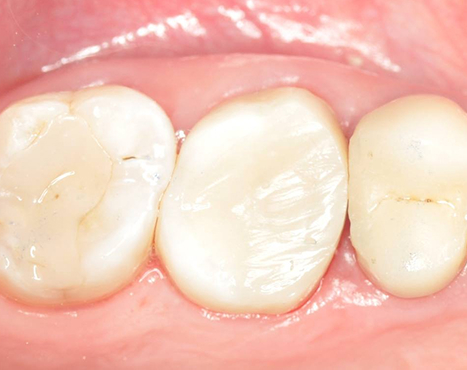

Результат: После проведённого эндодонтического лечения болевые ощущения при жевании устранены, дискомфорт и давление в области гайморовой пазухи исчезли, восстановилось нормальное носовое дыхание. Зуб сохранён, его функция восстановлена. После фиксации коронки полностью восстановлены анатомическая форма и жевательная эффективность, нагрузка распределяется корректно.

Стоматолог-ортопед: Калинин Антон Сергеевич